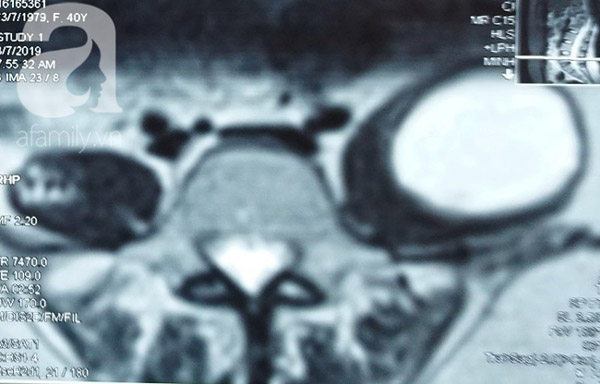

Hình chụp MRI áp xe cơ thắt lưng chậu của bệnh nhân.

Kết quả chụp MRI tại Bệnh viện cho thấy bệnh nhân A. bị lao cột sống 4 đốt D11-D12, L1-L2, có khối áp xe to dọc cơ thắt lưng chậu trái. Trước tình hình trên, bệnh nhân được chỉ định phẫu thuật ngay để tránh biến chứng.

Kíp mổ thuộc Khoa Ngoại Thần Kinh – Cột sống đã tiến hành phẫu thuật cho bệnh nhân bằng phương pháp dẫn lưu nạo vét hoại tử bã đậu trong ổ áp xe. Sau hơn một giờ phẫu thuật, 150ml mủ loãng và có nhiều bã đậu đã được lấy ra.